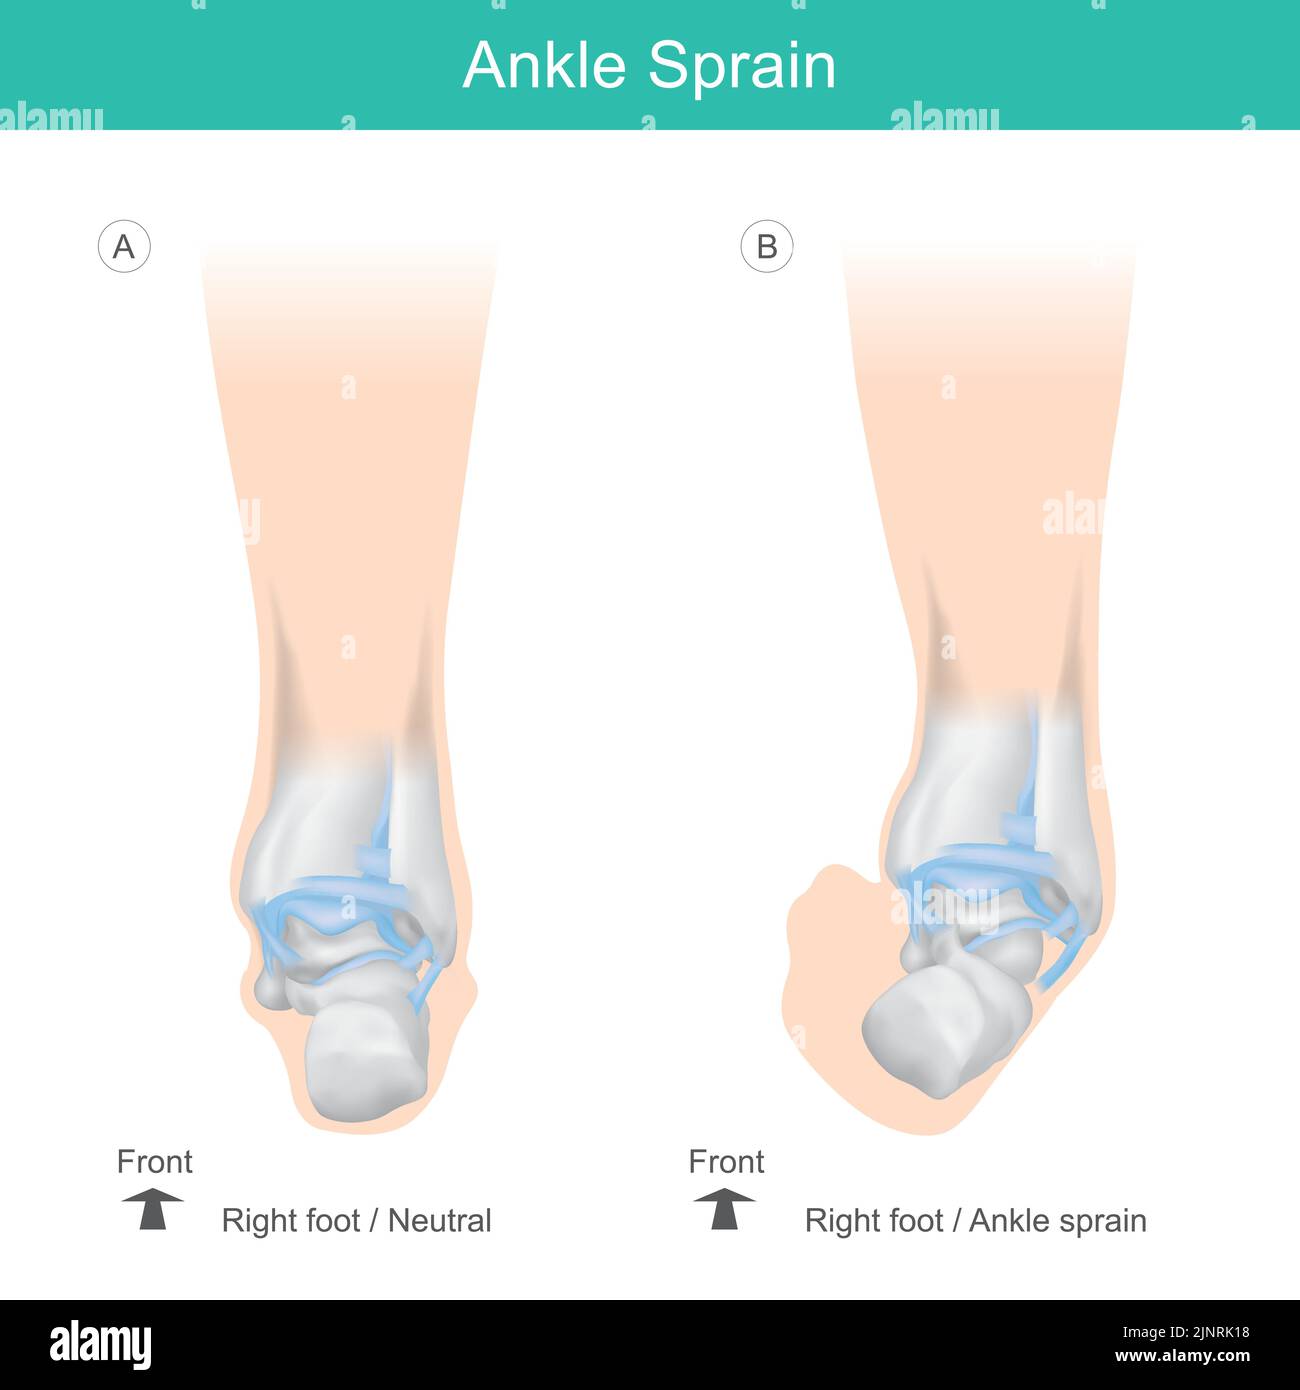

Ossa della caviglia dell'uomo. Posizionare correttamente le ossa della caviglia dell'uomo. Illustrazione assistenza sanitaria. Illustrazione Vettorialehttps://www.alamy.it/image-license-details/?v=1https://www.alamy.it/ossa-della-caviglia-dell-uomo-posizionare-correttamente-le-ossa-della-caviglia-dell-uomo-illustrazione-assistenza-sanitaria-image478107540.html

Ossa della caviglia dell'uomo. Posizionare correttamente le ossa della caviglia dell'uomo. Illustrazione assistenza sanitaria. Illustrazione Vettorialehttps://www.alamy.it/image-license-details/?v=1https://www.alamy.it/ossa-della-caviglia-dell-uomo-posizionare-correttamente-le-ossa-della-caviglia-dell-uomo-illustrazione-assistenza-sanitaria-image478107540.htmlRF2JNRK18–Ossa della caviglia dell'uomo. Posizionare correttamente le ossa della caviglia dell'uomo. Illustrazione assistenza sanitaria.